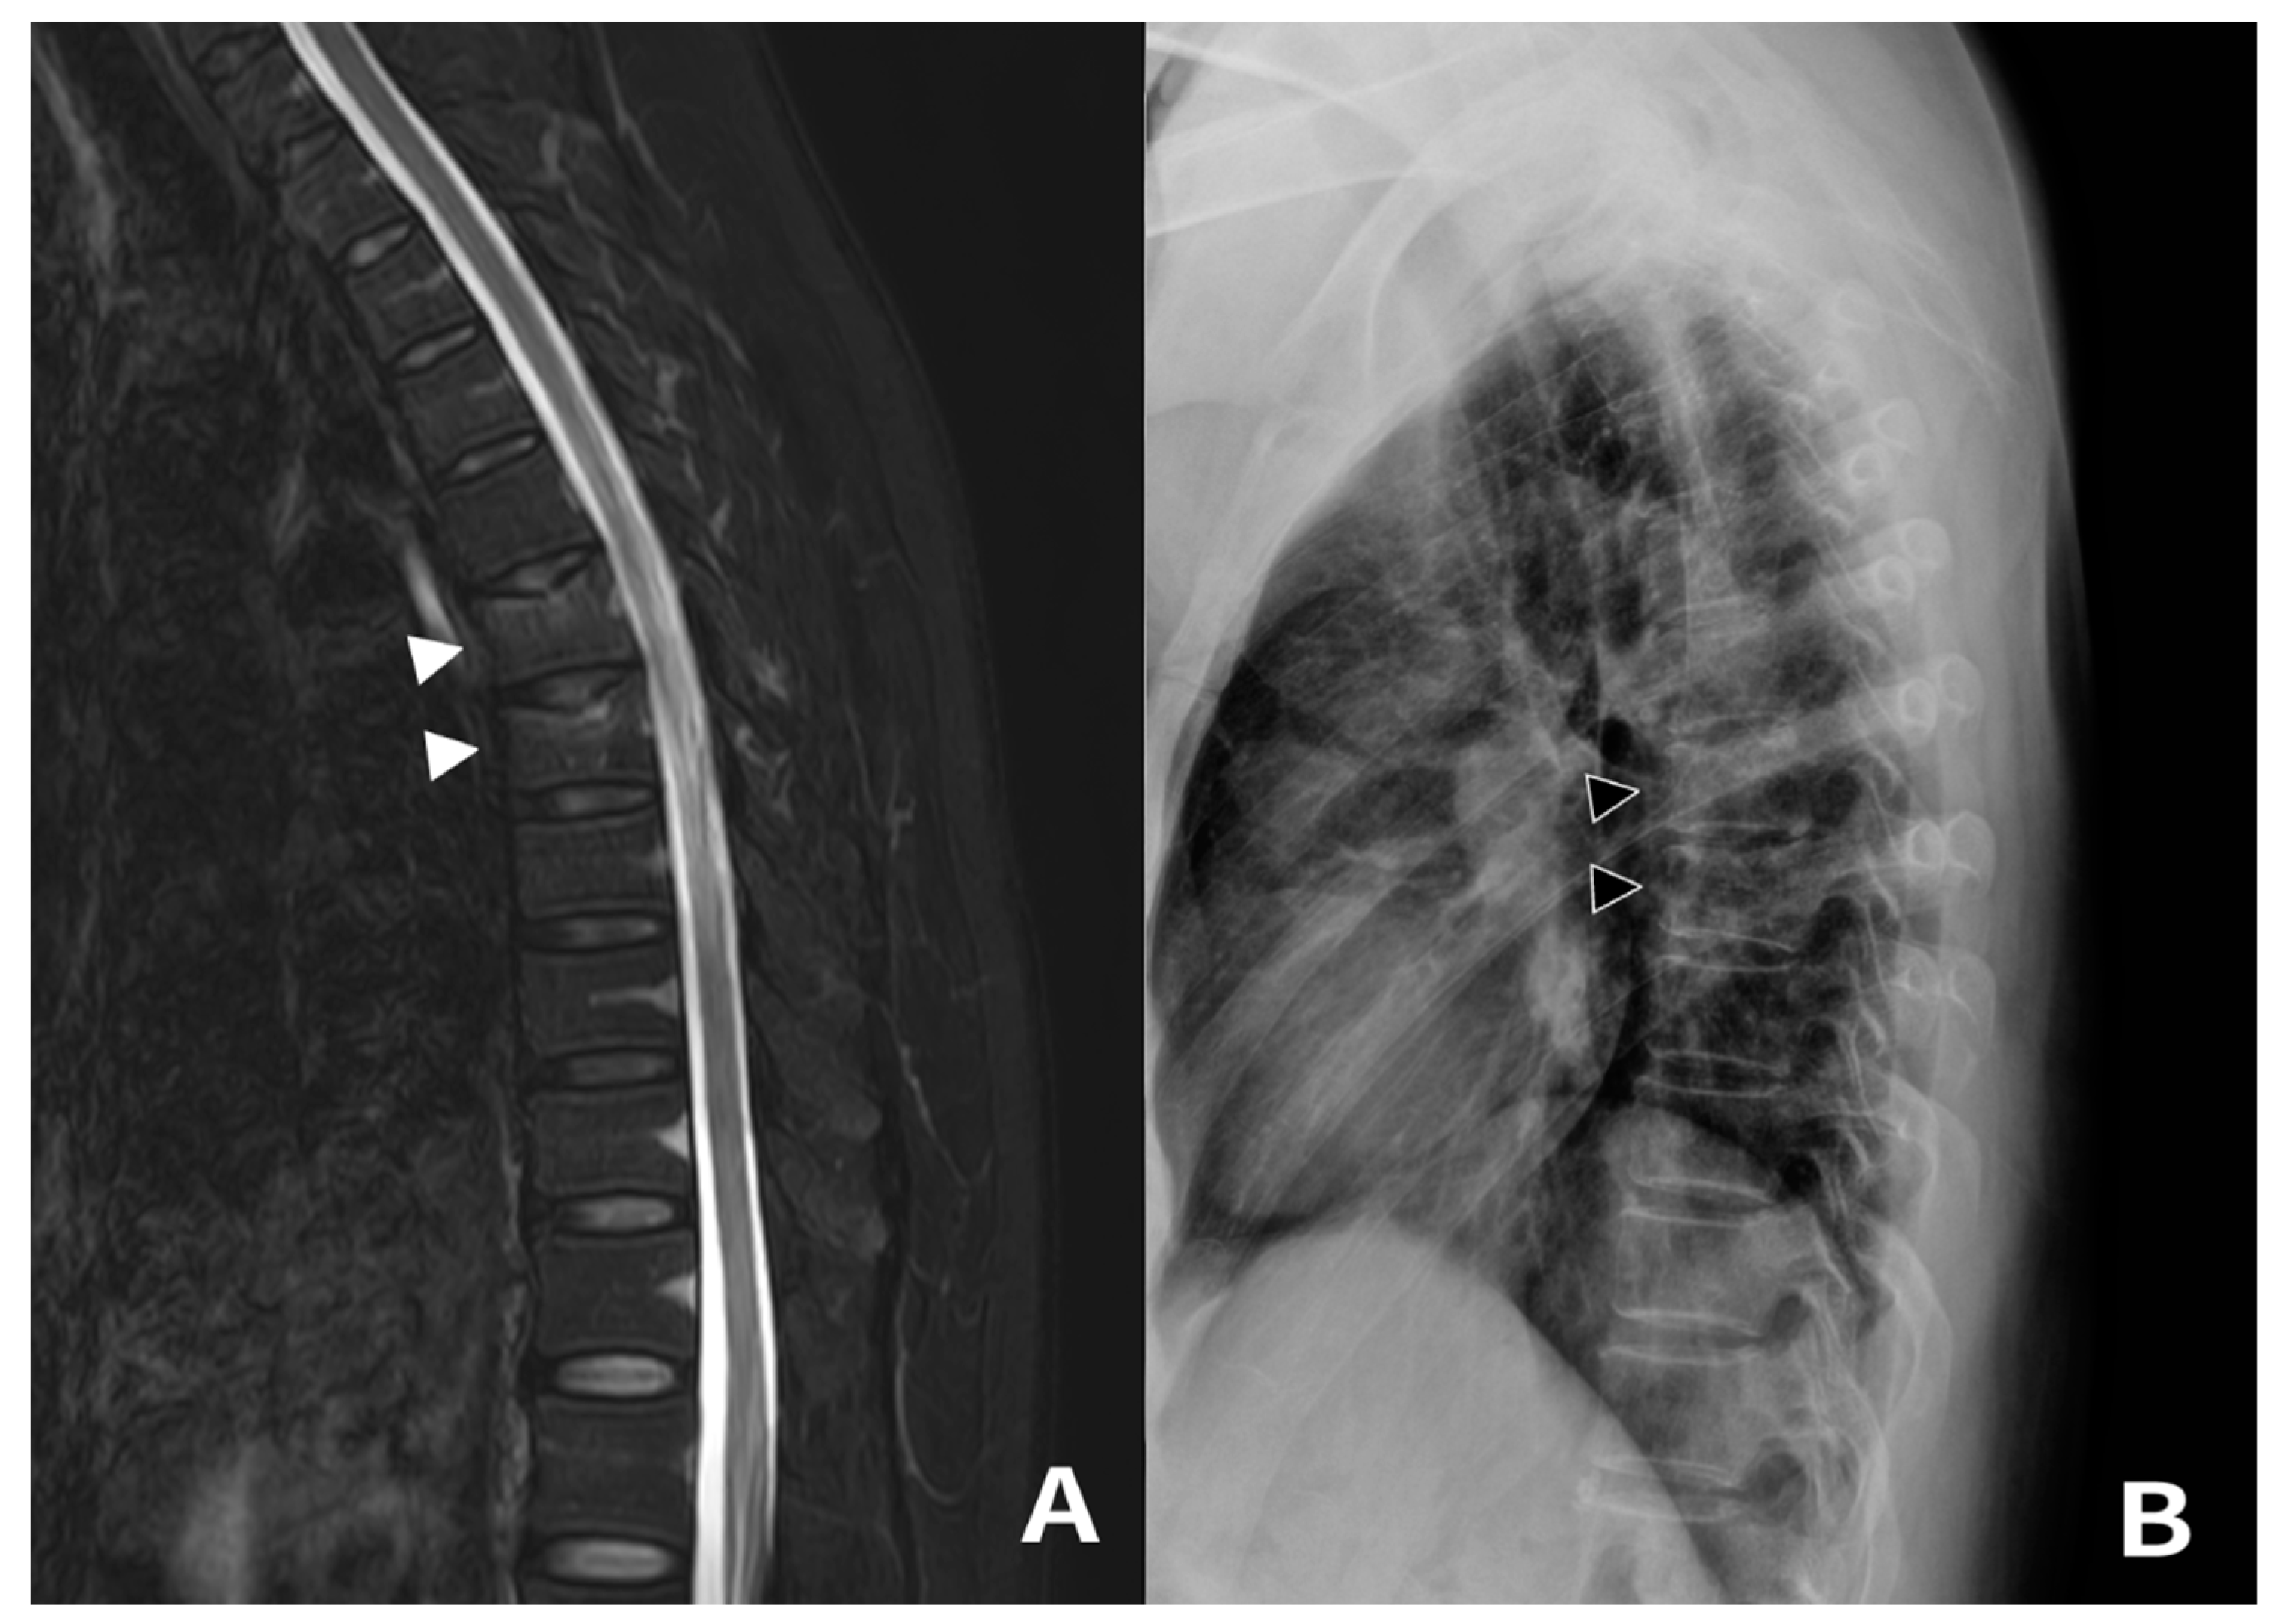

3.1. Case 1 and 2